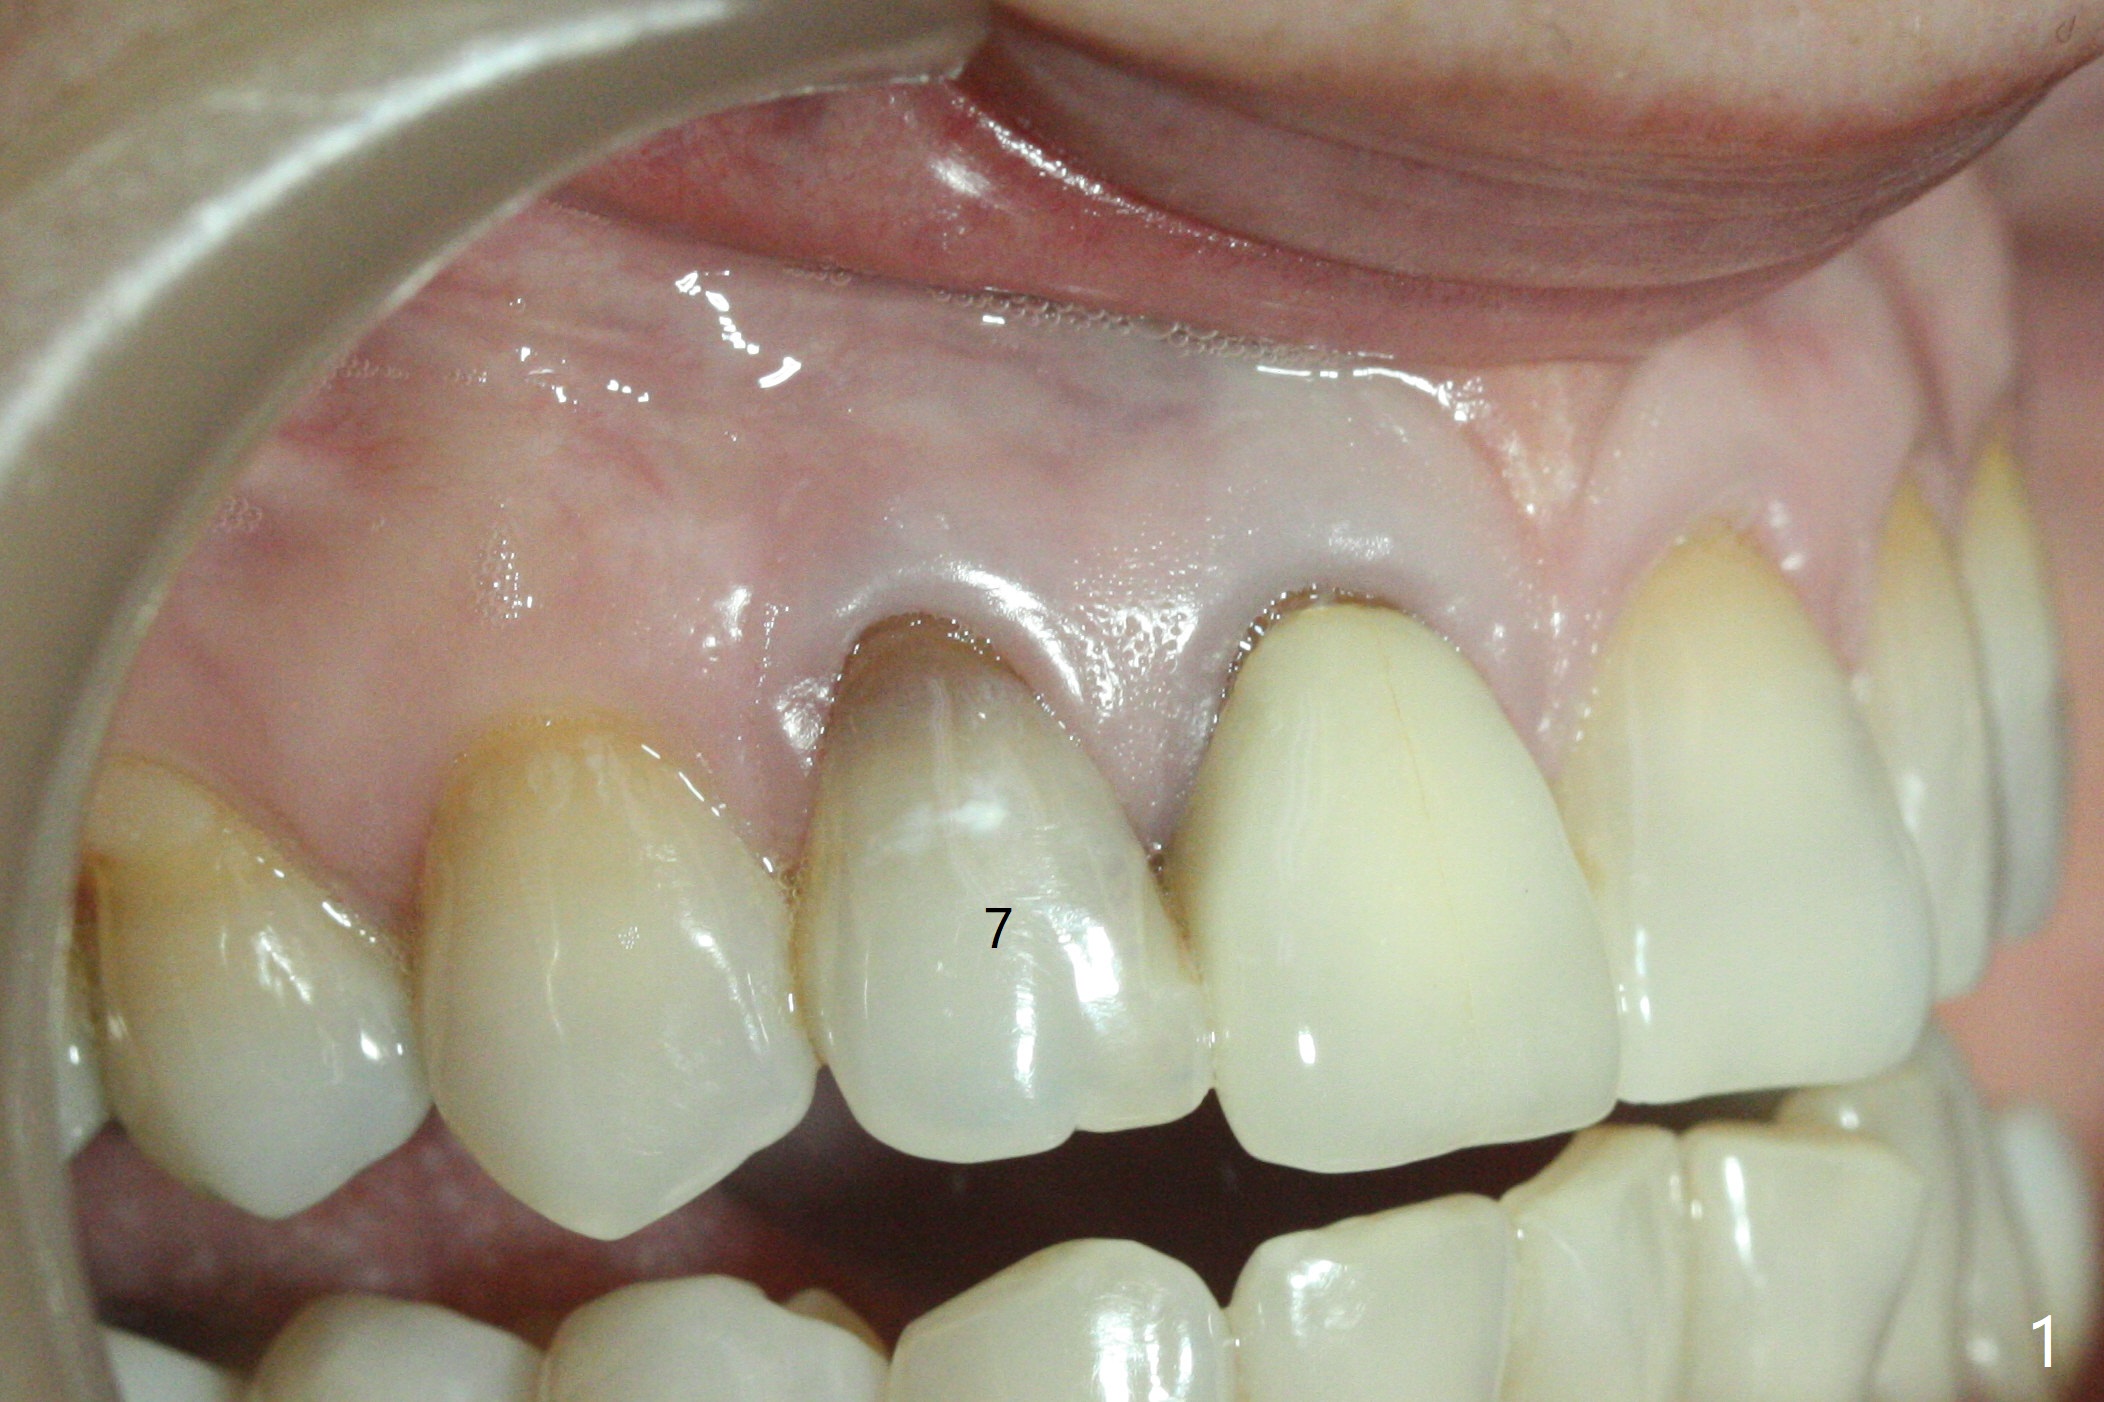

A 46-year-old woman requests a crown for the discolored tooth #7 (Fig.1,2) with mesiolingual composite (Fig.3 C) and periapical radiolucency (*). After RCT (Fig.4,5) with sodium hypochlorite, the tooth #7 is whiter than the ML composite (Fig.6,7). The patient returns 1 day post RCT for in house internal and external bleaching (Fig.8) with 35% hydrogen peroxide gel closed in the canal when she leaves. Three weeks later, the lateral incisor has the shade as the neighboring natural teeth (Fig.9,10). After the lightest shade composite placed in the canal and the access hole (Fig.11), the lateral looks better than the central with a crown and cervical discoloration (Fig.12).